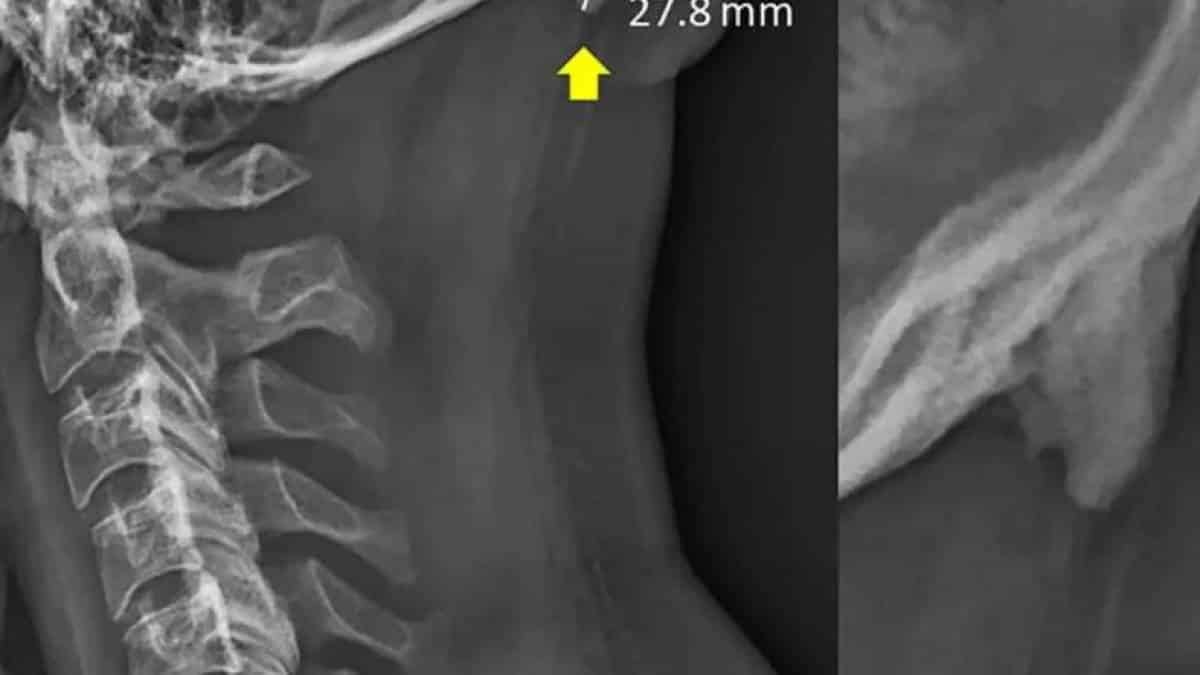

Os jovens estão desenvolvendo chifres na parte de trás de sua cabeça devido à postura incorreta. As causas estão sendo atribuídas ao uso de dispositivos portáteisQue a tecnologia transforma a maneira como realizamos diversas tarefas diárias a gente sabe, mas que ela pode mudar algo em nosso corpo é bastante preocupante. Diversas pesquisas no campo da biomecânica estão sugerindo que os jovens estão desenvolvendo chifres (sim, você não leu errado) na parte de trás de seus crânios. Na verdade, são esporões ósseos causados pela inclinação frontal da cabeça. A principal causa está sendo apontada como o uso de celulares e outros aparelhos portáteis. Quando usamos um aparelho qualquer, é normal que nosso pescoço fique curvado e esse desvio de postura pode causar um crescimento ósseo e de tendões na parte de trás do pescoço. Isso pode acontecer devido à transferência de peso da cabeça para apenas uma parte da coluna. Essa situação pode ser comparada à maneira como a pele engrossa a região de calos e outros traumas em resposta à pressão exercida naquele local. Como resultado de tudo isso, um gancho ou uma ponta semelhante a um cifre está crescendo e saindo do crânio de várias pessoas. Segundo cientistas da Universidade da Costa do Sol, na Austrália, essa pode ser a primeira documentação de uma adaptação fisiológica ou esquelética devido à penetração de tecnologia avançada na vida cotidiana. Eles disseram ainda que os smartphones e outros dispositivos portáteis são os principais responsáveis pelo corpo humano estar se "contorcendo" ao exigir que usuários inclinem suas cabeças para entender o que está acontecendo nas telas em miniatura. Mesmo com o estranhamento causado, David Shahar, um dos autores do estudo, alerta que essa formação incomum é um grave sinal de que a postura do indivíduo está totalmente incorreta, e que isso pode lhe causar sérias dores de cabeça crônicas, além de dores na parte superior da coluna e no pescoço. Os mais afetadosO estudo vem sendo realizado desde 2016. David contou que eles tiveram amostra de 218 raios X de pessoas de 18 a 30 anos, onde foi observado que o crescimento ósseo foi visto em 41% dos resultados, muito mais do que as projeções iniciais dos pesquisadores. Outra característica bastante reveladora foi que a condição prevalece entre os homens. Nas mulheres isso não foi muito comum. Esses resultados levantam questões alarmantes sobre a nossa postura e o quanto estamos deixando que a tecnologia esteja presente em nossas vidas. Os que mais devem se preocupar com isso são as pessoas que usam algum tipo de tecnologia desde pequenos. "Essas formações demora muito para se desenvolver, então isso significa que aqueles indivíduos que sofrem com elas provavelmente têm forçado essa área desde a infância", explicou David. Há algum meio de evitar?Segundo os cientistas envolvidos na pesquisa, "a resposta não é banir a tecnologia, há maneiras menos drásticas". Eles enfatizam a conscientização da população sobre o uso indiscriminado da tecnologia e de seus danos à estrutura óssea. "Todos os que usam a tecnologia durante o dia devem adquirir o hábito de 'recalibrar' sua postura durante a noite", diz o estudo. Neste momento você deve ter ficado preocupado com isso, certo? Você mesmo pode verificar o surgimento desse "chifre", basta passar a ponta dos dedos próximo a área onde há o encontro do pescoço com a coluna, caso seja constatada alguma protuberância ou precipitação na região, o conselho é o de procurar um médico para avaliar a condição. Via: The Washington Post |